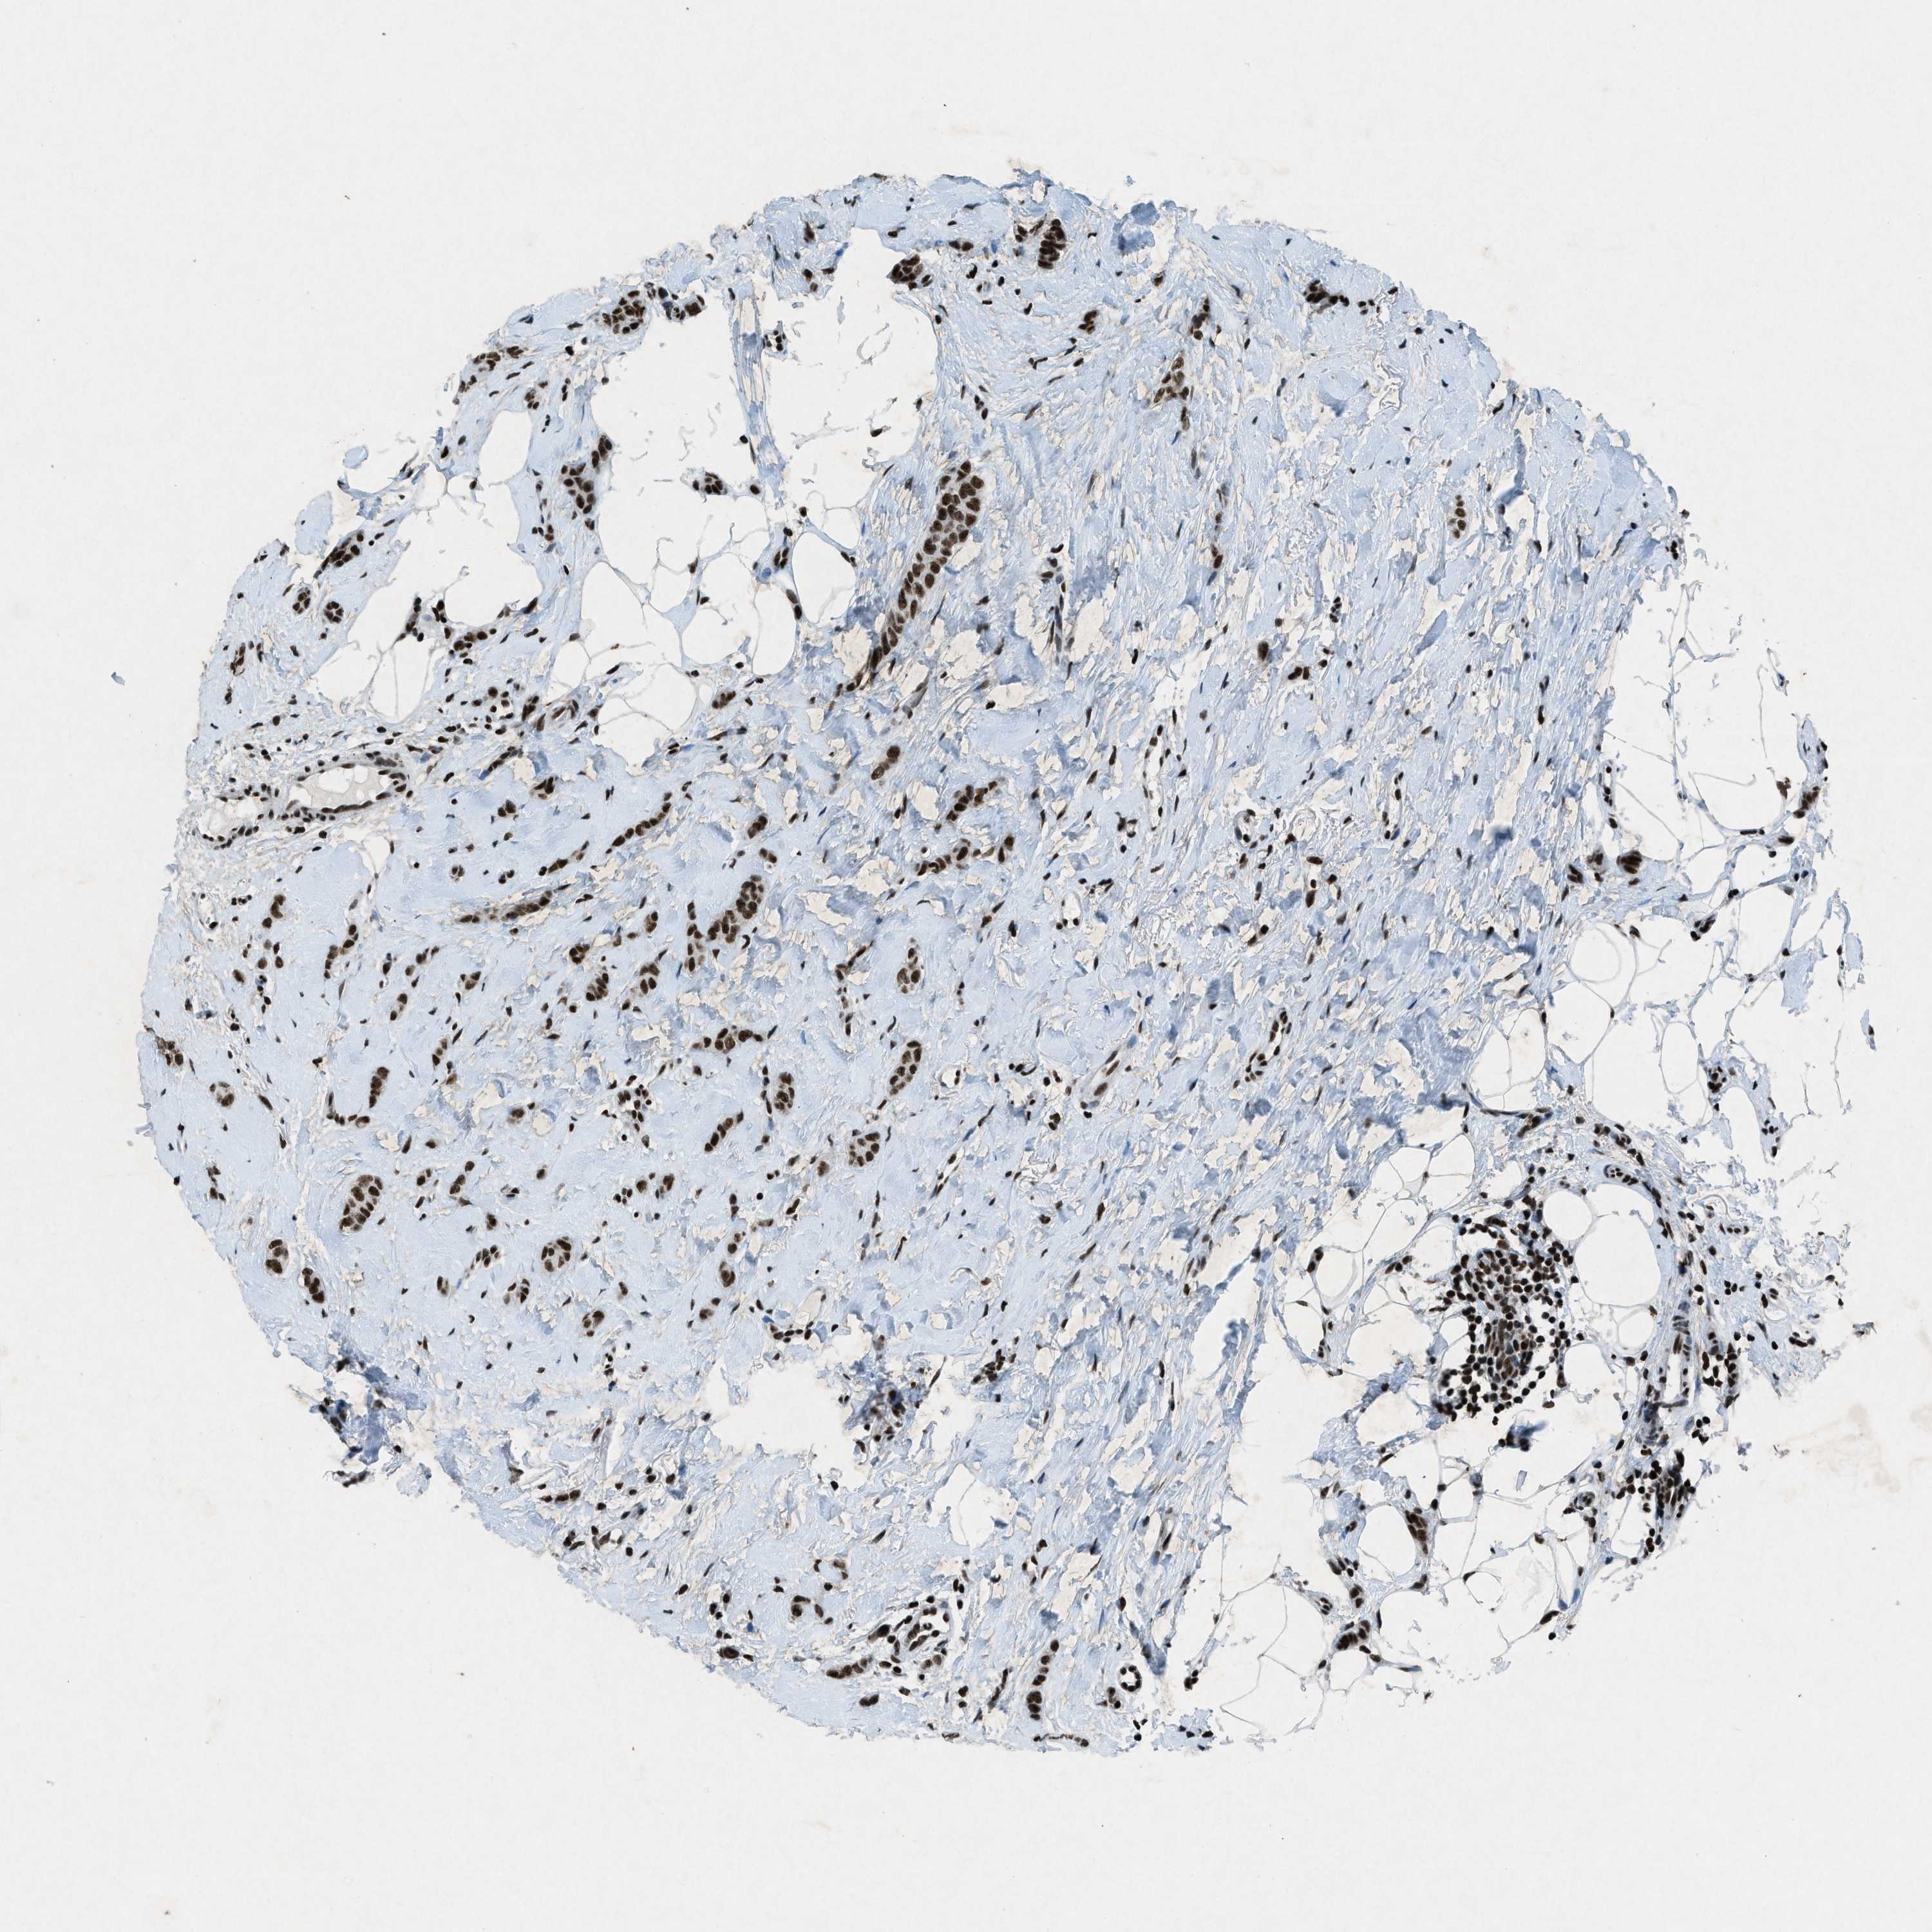

BRCA TCGA BRCA VALIDATION PROTEIN EXPRESSION